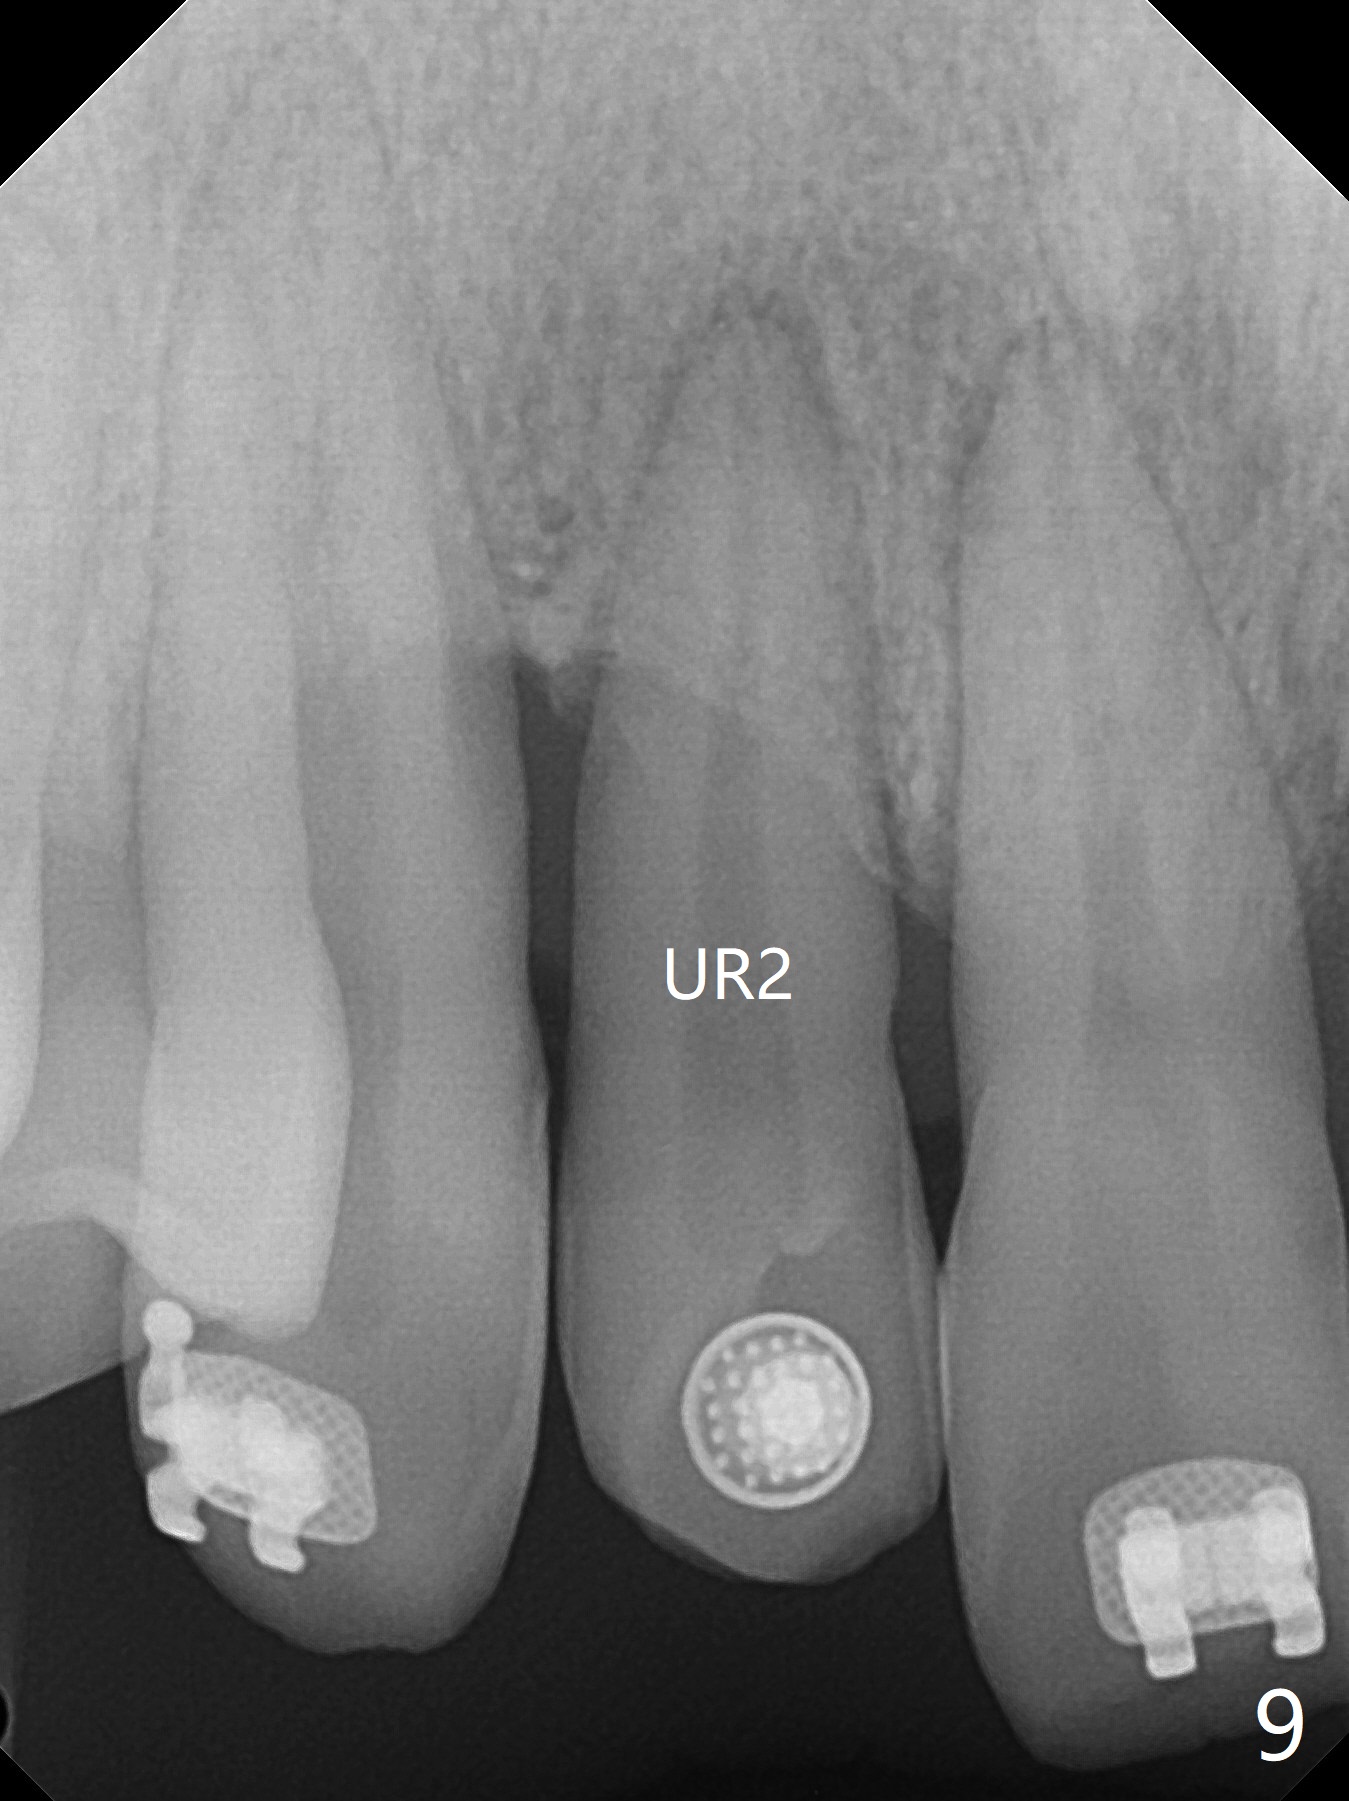

Reduction